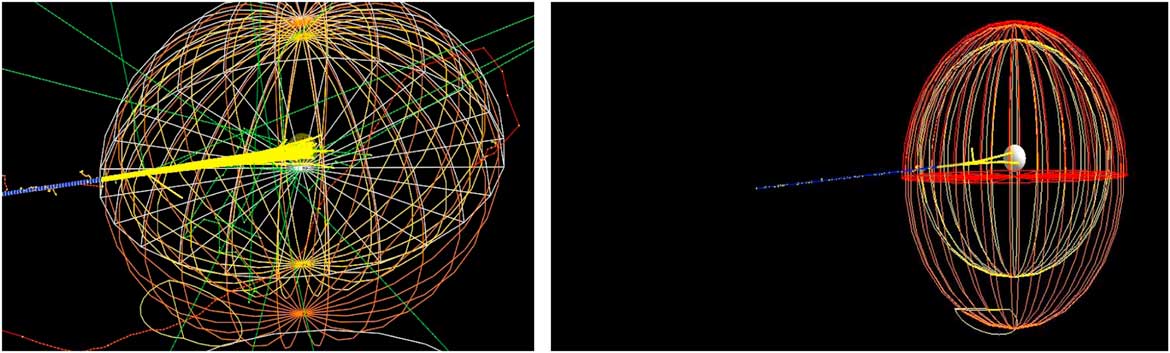

Our main study is to investigate the effect of bio-NMs injected into a tumour during a proton therapy. For this, we have simulated a spherical tumour localised in the centre of a human head. Then, the human head is exposed to a monoenergetic proton beam placed at 1 m from a patient (see Figure 1).

Figure 1 Monte Carlo simulation of 106 beam interaction with a human head.

Proton therapy was simulated with the Monte Carlo code of a tumour within a human head. The tumour is assumed to have a spherical shape with a diameter of 1·5 cm and localised at the centre of the head (see Figure 1). The best way to inject NMs in a tumour localised in a sensitive organ like a human head is by the bloodstream. Carmeliet et al.Reference Carmeliet and Jain 21 and Avnesh et al. (2013)Reference Thakor and Gambhir 22 studied the development of blood vessels in the tumour cells; they noticed that the blood vessels are more concentrated in the centre of a tumour. Consequently, NMs will be distributed with a non-homogeneous way and concentrated more towards the centre of the tumour. In this simulation, the concentration of NMs in the tumour is assumed ranging between 0 and 4%. Figure 2 shows the concentrations of bio-NMs localised in a tumour taken in our simulation.

Figure 3 shows processes that occur during a simulation of 106 proton through a head containing GNPs within tumour. In order to have the Bragg peak energy exactly in the tumour location, the proton beam energy should be in the energy range between 116 and 132 MeV. We notice here that processes such as electron-ion and multi-scattering of electrons are the most dominating in our simulation. These are due to secondary electrons created by NMs when irradiated by proton beams. Chow et al.Reference Chow, Leung, Fahey, Chithrani and Jaffray 13 have calculated secondary electrons outside and inside GNPs irradiated by low-energy electrons at cellular level, similarly Walzlein et al.Reference Walzlein, Scifoni, Kramer and Durante 23 have calculated secondary electrons created from heavy atom NPs irradiated by proton. They both concluded that the additional of secondary electrons from NMs may enhance the dose absorption.

Figure 3 Physical processes generated during a proton therapy. Abbreviations: e-ion, electron-ion; multi-scatt-e, multi-scattering of electrons.